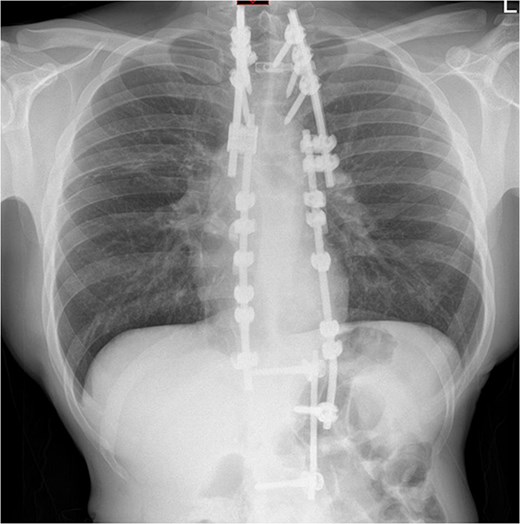

Four days after the surgery, the patient was re-admitted due to fever, cough, and some small-volume purulent discharge from his drain site. A repeat chest radiograph (Fig. 4) was unremarkable, and a wound swab was negative. He was empirically treated with 24 hours of intravenous antibiotics and given a short 4-day course to complete at home. It was felt by the team that a lower threshold for treatment of infection would be appropriate, given his diagnosis of CIP. He was discharged 1 day after re-admission and made a good recovery.

Repeat chest radiograph on re-admission to hospital with fevers and tachycardia.